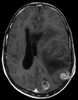

Radiation therapy or radiotherapy, often abbreviated RT, RTx, or XRT, is a therapy using ionizing radiation, generally as part of cancer treatment to control or kill malignant cells and normally delivered by a linear accelerator. Radiation therapy may be curative in a number of types of cancer if they are localized to one area of the body. [Source: Wikipedia ]